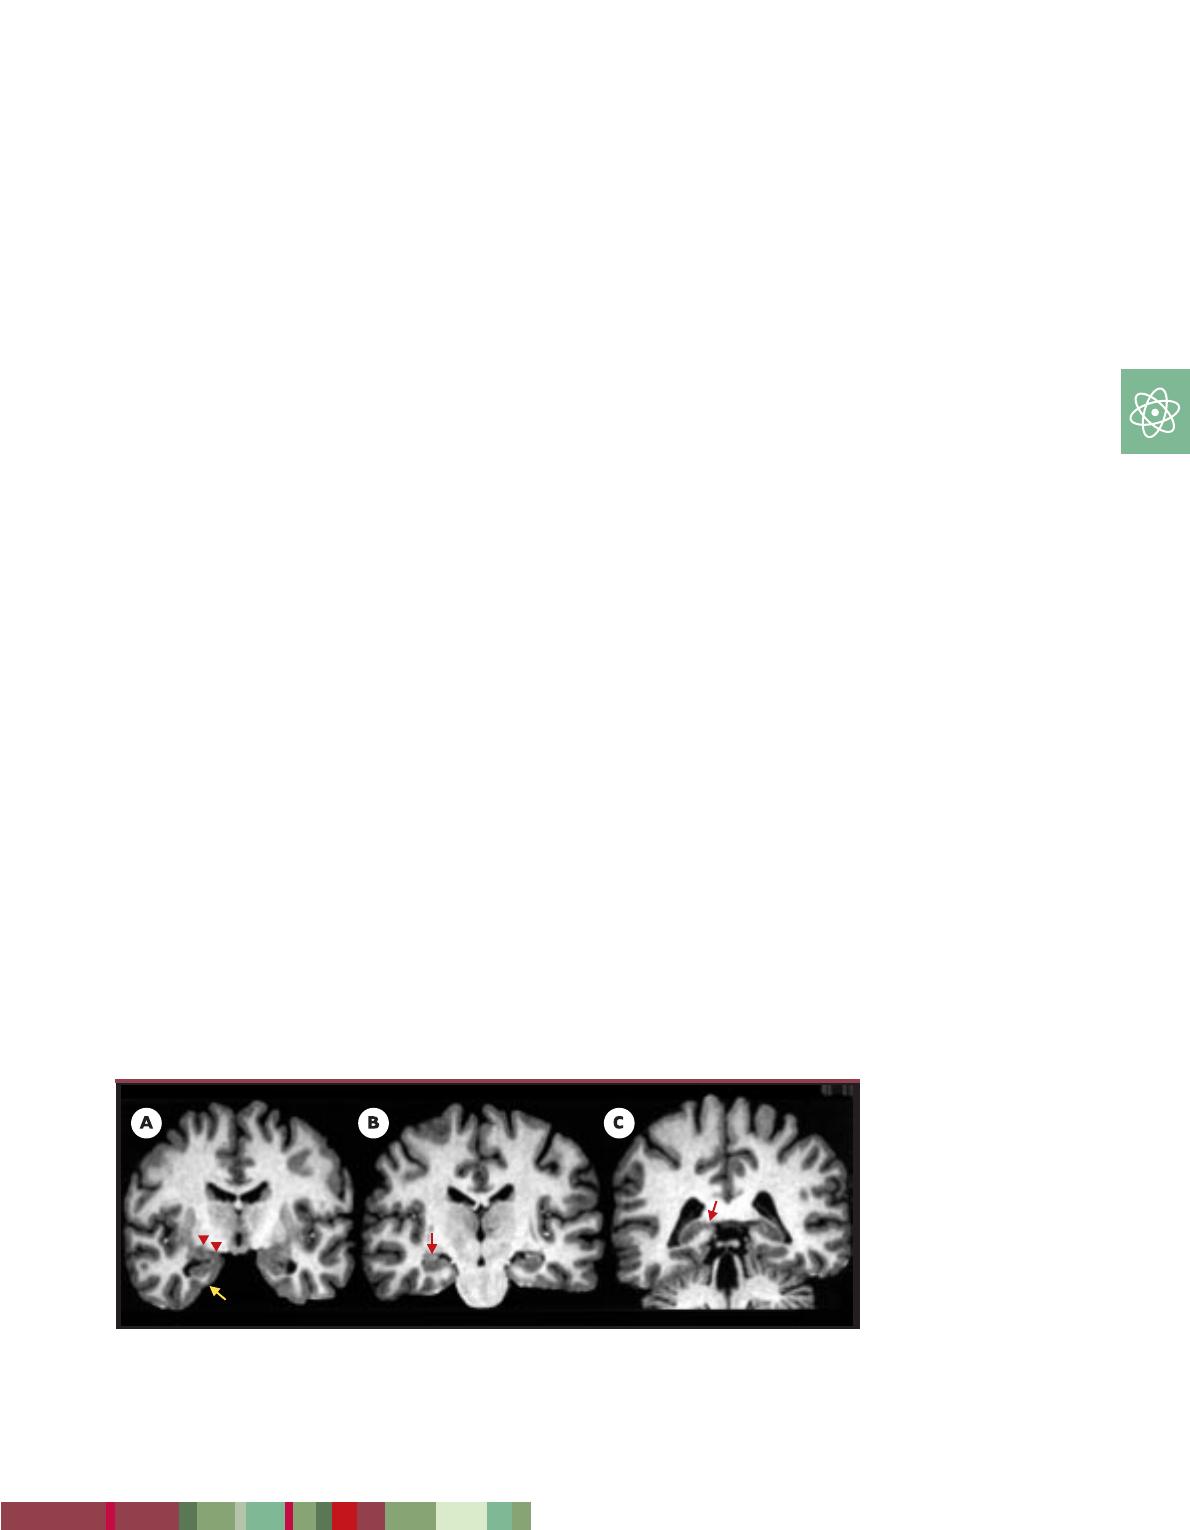

Figure 4. Anatomie hippocampique par IRM. Coupes coronales obliques perpendiculaires au grand axe des for-

mations hippocampiques passant par l’uncus (A), le corps (B) et la queue (C) de l’hippocampe. Les formations

hippocampiques sont indiquées par les flèches rouges, l’amygdale par la flèche jaune.